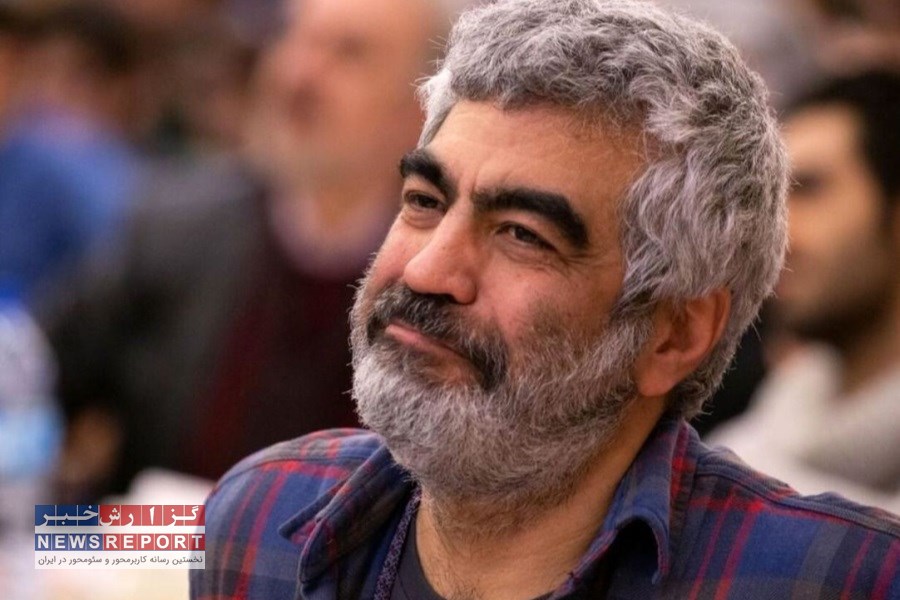

به گزارش خبرنگاران گروه جامعه گزارش خبر، دکتر «اورنگ ایلامی» با اشاره به اینکه روتاویروس یکی از شایعترین عوامل عفونتهای گوارشی در کودکان است که میتواند به کمآبی شدید، بستری شدن در بیمارستان و در مواردی مرگ و میر منجر شود، افزود: واکسیناسیون علیه این ویروس از سوی وزارت بهداشت به عنوان بخشی از برنامه ملی واکسیناسیون در کشور معرفی شده است.

سرپرست معاونت بهداشت دانشگاه علوم پزشکی شیراز با بیان اینکه اجرای این برنامه گامی اساسی در راستای ارتقای سلامت کودکان و کاهش بار بیماریهای عفونی گوارشی است، گفت: واکسن روتاویروس در سه دوز و طبق برنامه مشخص به کودکان زیر یک سال ارائه میشود تا ایمنی مناسبی در برابر این بیماری ایجاد شود.

دکتر ایلامی همچنین افزود: کودکان، این واکسن پنج ظرفیتی را در سه نوبت دو ماهگی، چهار ماهگی و شش ماهگی، به میزان دو میلی لیتر و به صورت خوراکی دریافت می کنند.

این مقام مسوول در حوزه بهداشت دانشگاه علوم پزشکی شیراز برنامه واکسیناسیون کودکان را از جمله موفقترین دستاوردهای بهداشت عمومی در سراسر جهان دانست و ادامه داد: با اجرای واکسیناسیون علیه بیماریهای مختلف، موارد ابتلا و مرگ و میر ناشی از این بیماریها به شدت کاهش یافته است.